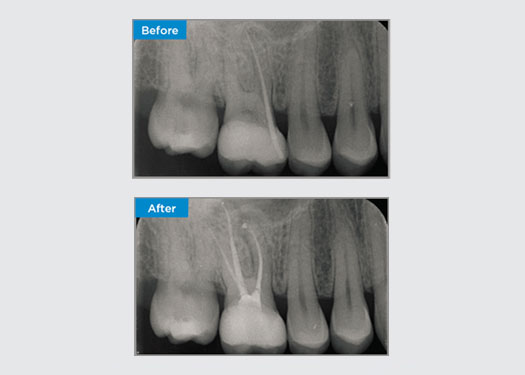

Casos clínicos

Los médicos de todas partes de Australia y Nueva Zelanda comparten amablemente presentaciones relevantes, interesantes y, a veces, desafiantes para los pacientes, junto con su selección de materiales y métodos para optimizar los resultados de sus pacientes.